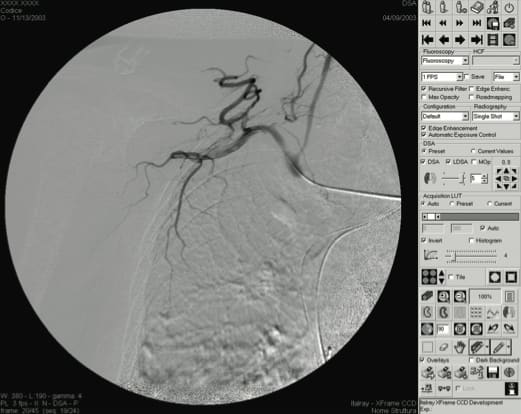

Radiology and fluoroscopy applications present several challenging machine vision requirements. One is the need to acquire and process in real time huge sequences of hundreds of images so that doctors can review them on the fly, a task that is not easily accomplished by many vision systems. In Digital Subtraction Angiography (DSA), for example, the difference between the acquired image and a reference image is displayed on-screen so that doctors can trace the path of the contrast media in the vessels. As the original images are being processed, they must also be stored simultaneously to the system’s hard disk.

The X-Frame CCD digital fluoroscopic systems incorporate a 9", 12", 14", or 16" triple-field QX series image intensifier. The image intensifier produces x-ray images that are acquired by a 1024 × 1024 × 12-bit CCD camera connected to an image acquisition board by DALSA, which provides high-speed image acquisition of up to 60 frames per second (fps). The x-ray images are then sent to a vision processor for real-time processing, primarily recursive filtering and edge enhancement. “The DALSA vision engine with its independent processor is very useful because it can be dedicated to real-time processing without overloading the host system, which is used for display and storage,” said Rebuffat.

After processing, the images are transferred back to the host system, where they are converted to 8-bits for display on an 18" flat-screen monitor with monochrome LCD designed specifically for medical imaging and saved in the original 12-bit format. The system provides 15 fps storage at maximum resolution, and 30 fps storage at 1024 x 512 x 12, and can archive up to 15,000 images. Medical personnel can retrieve the saved images from the hard disk and manipulate them in a variety of ways, including filters, LUTs, rotations, flip, and mirror.

Also, while in traditional systems, the image intensifier/CCD camera images are circular, resulting in a black band of wasted space outside of the image circle (see previous image), acquired images from a dynamic flat-panel detector system are rectangular in which the acquired image area all contains useful information. Dynamic flat-panel detector technology offers additional benefits, including higher dynamic range (16 bits instead of 12), higher spatial resolution, a reduction in patient dose, and size compactness.